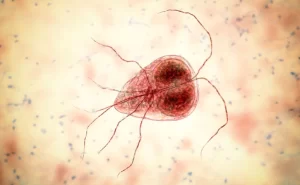

A amebíase intestinal pode ser assintomática, com infecções autolimitantes, ou pode ser sintomática, com: Colite amebiana (inflamação...